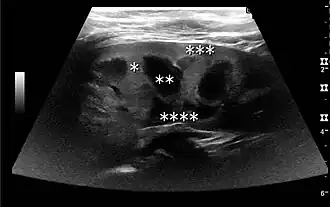

In the longitudinal scan plane, the kidney has the characteristic oval bean-shape. The right kidney is often found more caudally and is slimmer than the left kidney, which may have a so-called dromedary hump due to its proximity to the spleen. The kidney is surrounded by a capsule separating the kidney from the echogenic perirenal fat, which is seen as a thin linear structure.[1]

The kidney is divided into parenchyma and renal sinus. The renal sinus is hyperechoic and is composed of calyces, the renal pelvis, fat and the major intrarenal vessels. In the normal kidney, the urinary collecting system in the renal sinus is not visible, but it creates a heteroechoic appearance with the interposed fat and vessels. The parenchyma is more hypoechoic and homogenous and is divided into the outermost cortex and the innermost and slightly less echogenic medullary pyramids. Between the pyramids are the cortical infoldings, called columns of Bertin (Figure 1). In the pediatric patient, it is easier to differentiate the hypoechoic medullar pyramids from the more echogenic peripheral zone of the cortex in the parenchyma rim, as well as the columns of Bertin (Figure 2).[1]

Figure 1. Normal adult kidney. Measurement of kidney length on the US image is illustrated by '+' and a dashed line. *Column of Bertin; ** pyramid; *** cortex; **** sinus.[1]